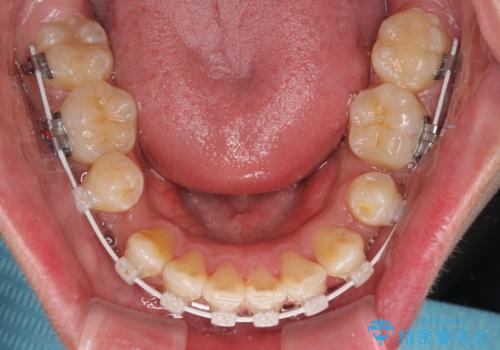

上下左右の小臼歯を抜歯し、歯列を整えるためのスペースを確保

左下は第二小臼歯に根管治療歴があったため、左下のみ第二小臼歯を抜歯しアンカースクリューを併用

それ以外の部位は第一小臼歯を抜歯

矯正中の見た目を気にされていたため、プラスチックブラケット+コーティングワイヤーを使用した、目立ちにくい審美矯正装置を選択しました。